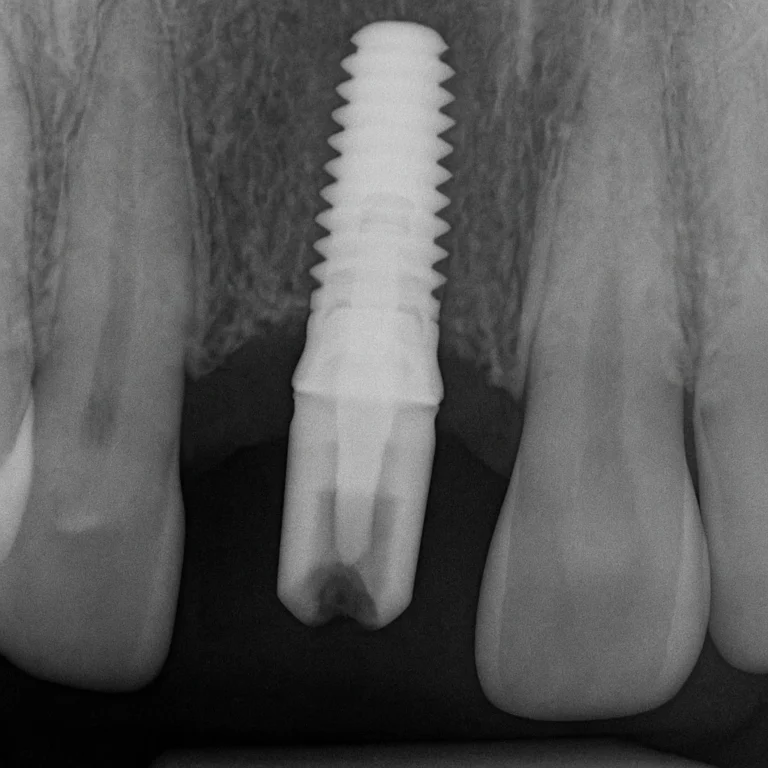

Implantologia è una sostituzione sicura dei denti mancanti.